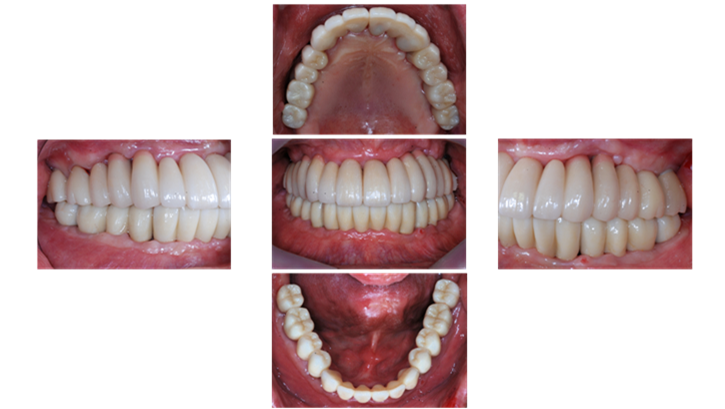

Clinical case: Preview the final goal first, make the ideal treatment plan, then realize it using the appropriate tools

- Courtesy of Dr. Sang Tack Lee, Korea -

Dr. Sang Tack Lee, edentulous, digital full mouth prosthetics, digital guided surgery, #11, #13, #14, #16, #17, #21, #23, #24, #26, #27, #33, #34, #36, #37, #43, #44, #46, #47, guided surgery, flapless, AnyRidge, R2GATE, Mega ISQ, MEG Torq, MEG Engine, R2GATE Full surgical kit

AnyRidge implant system, R2GATE Guide, R2GATE full surgical kit , Mega ISQ